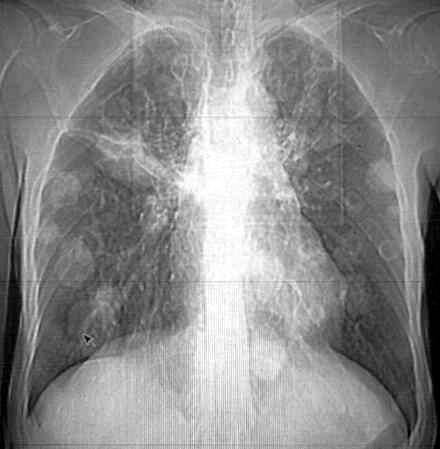

男62肺癌治疗后复查

具体治疗措施不清楚,治疗前空洞很少,请讨论空洞的性质

双肺内及胸壁旁见有多发软组织实性阴影和空洞,实性病变多见有脐凹切迹,贴近胸膜的见有胸膜凹陷征;空洞的壁多为厚薄不均,形态不规则,纵隔内见有较多肿大淋巴结,诊断为双肺内转移性病变。

肺癌肺内转移,右肺门转移,建议ct增强

右肺门软组织块影,右主支气管及中间段支气管管壁明显增厚,两肺内多发结节及大小不等的类圆形薄壁空洞,纵隔内多发肿大的淋巴结;

考虑:1.右中央型肺癌伴两肺广泛性转移及纵隔转移。

2.多发性空洞需和霉菌性空洞鉴别。